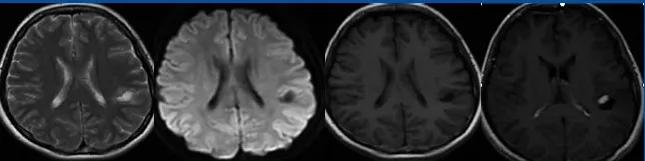

肥胖细胞型星形细胞瘤(GemA)瘤体可较大,信号不均,占位效应及瘤周水肿明显,增强扫描明显不均匀强化

病例展示

38Y/M

主诉:突发意识不清伴肢体抽搐 1 次

右侧额叶胶质瘤切除标本:结合免疫组化结果诊断肥胖型弥漫星形细胞瘤,WHO2 级,IDH 突变型